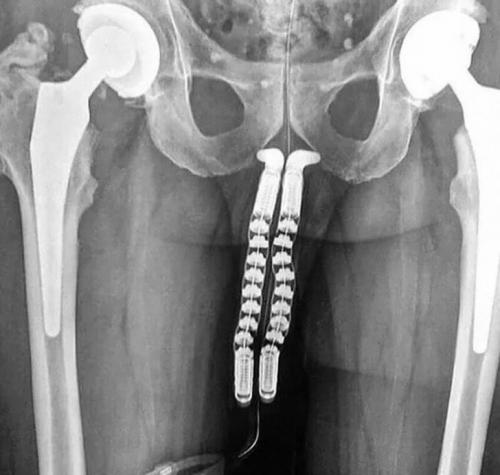

На фото процесс смены пола: вы видите рентген-снимок пациента на этапе трансплантации полового органа